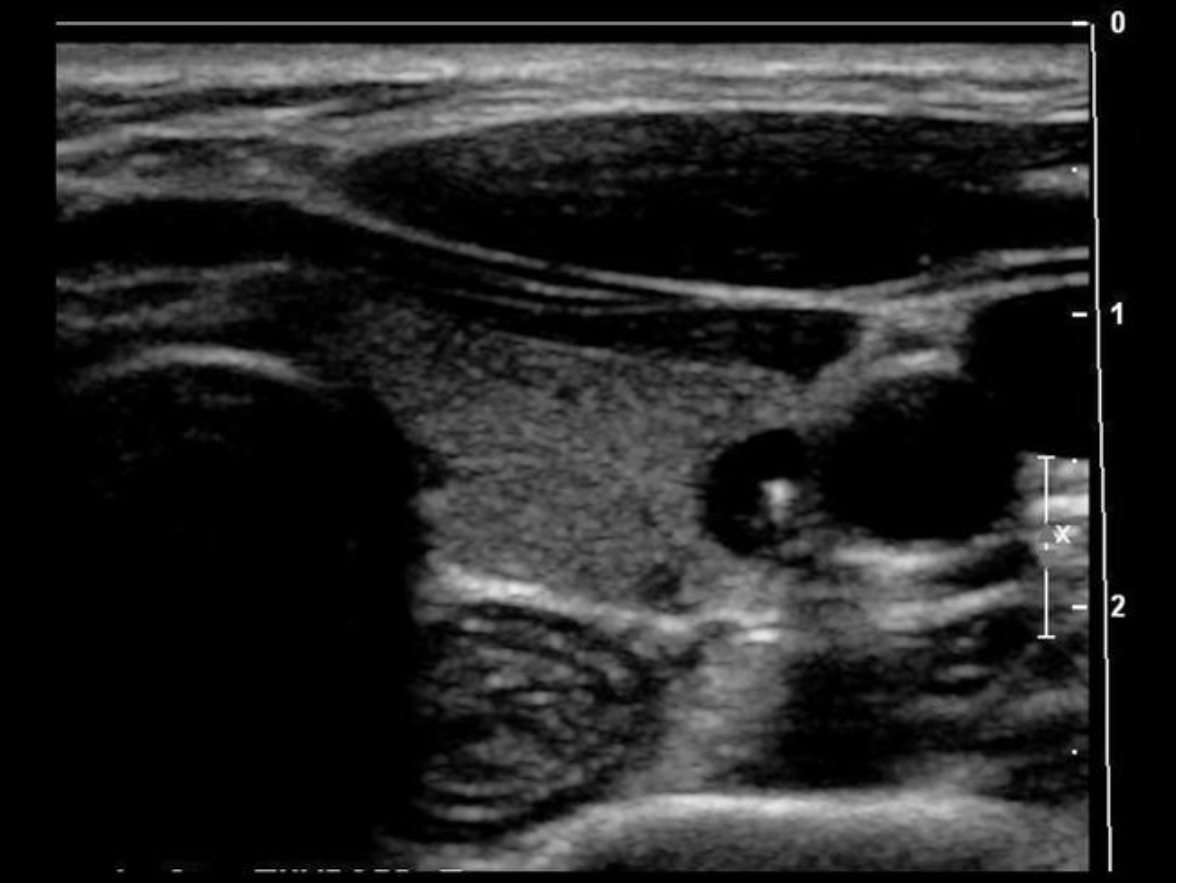

Find the mediastinum testis

The mediastinum testis is an infolding of the tunica albuginea that enters the posterior testicle. Blood vessels and tubules enter and exit the testicle through the mediastinum. testis. and it can be considered the hilum of the testicle.

What structure is indicated by the arrow?

D. mediastinum testis

Folds of the tunica albuginea form sections within the testes that converge at a single location called the mediastinum testis (similar to a hilum). The rete testes is a series of channels within the mediastinum. Blood vessels and ductules enter/exit the testicle at the mediastinum.